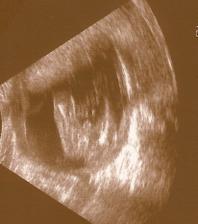

Naše milá rozrůstající se rodinka :o))

Začalo to v dubnu 1999 a zpečetili jsme to nejdříve narozením našeho syna Adámka a poté svatbou 1.10.2005, za chvíli budeme mít první výročí 🙂